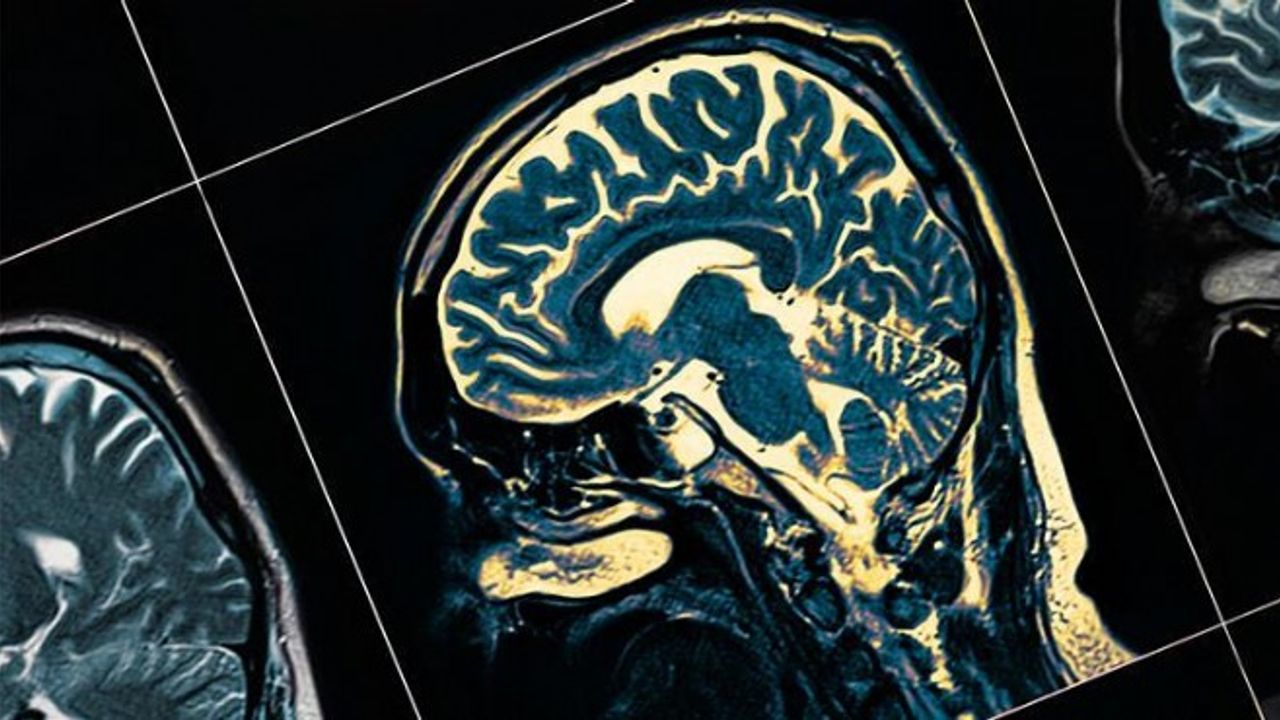

Yaygın görülen bir demans türü olup beyin hücrelerinin yok olmasına neden olan ilerleyici bir nörolojik hastalık olarak bilinen Alzheimer'ın dünya genelinde yaklaşık 50 milyon kişinin hayatını etkilediği biliniyor. Düşünce, hafıza ve davranış fonksiyonlarında azalmaya neden olan Alzheimer'ın kesin nedeni bilinmezken, etkin bir tedavi yöntemi de bulunmuyor.